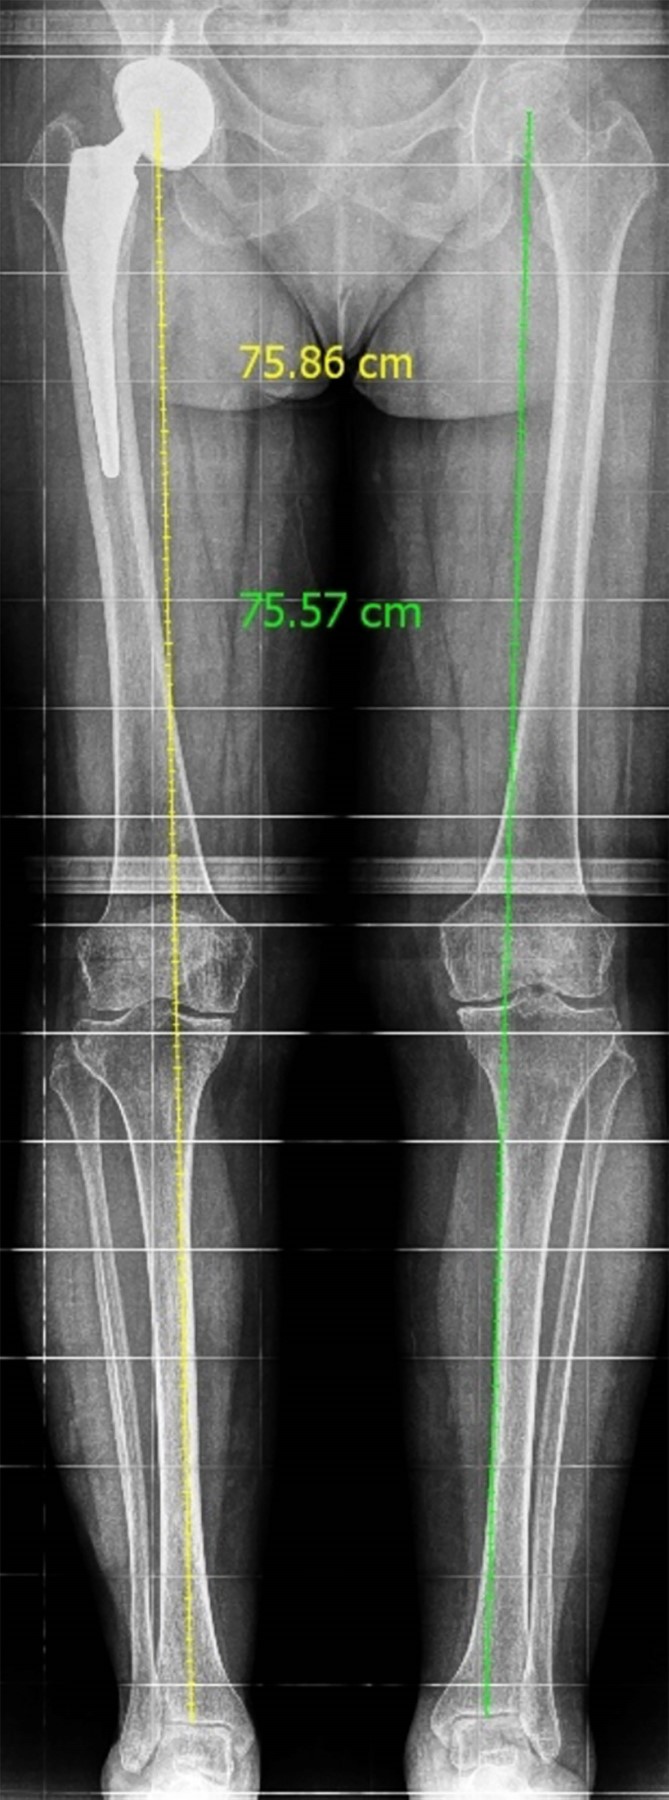

Se realizó seguimiento a las dos, cuatro y ocho semanas, sin encontrar sintomatología local ni sistémica. A los seis meses de postoperada, la paciente presentó marcha sin alteraciones, sin dismetría de miembros pélvicos y sin dolor referido. Se valoró mediante la escala de Harris modificada, obtuvo un puntaje de 82, que se define como un resultado bueno. Posteriormente, se llevó a cabo un seguimiento postoperatorio de 12 meses, durante el cual la paciente mostró progresión clínica satisfactoria con mejoras en los rangos de movimiento. No se observaron anomalías en la marcha y la paciente informó la ausencia de dolor. El puntaje de cadera Harris modificado se volvió a calcular, obteniendo una puntuación de 90, el cual se define como un resultado excelente. Además, se realizó una escanometría de control anual donde se encuentra implante sin datos de aflojamiento a nivel pélvico ni femoral, sin acortamiento de extremidades (Figura 5).

Figura 5